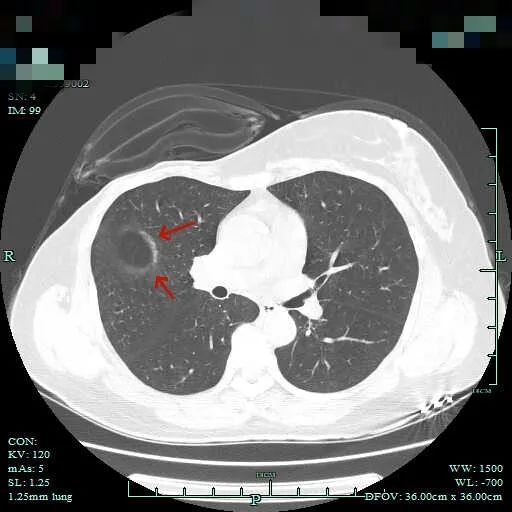

再看这次入院后在本院复查的平扫片子:

这个病灶在外院的报告是提示较既往的片子有增大进展的,但我们没有见到以前的影像。不过影像科报有增大进展,加上此次影像上看明显是混合密度,且边缘毛糙不平,细毛刺明显,血管穿行与进入也明显,何况紧贴叶间裂,若确实恶性,那是极容易胸膜种植转移的!这病灶放着那是睡不着觉的,所以我们建议其手术切除。术前还在想,如果术中发现胸腔内已经有种植转移,那么病灶单纯切除以取得病灶,指导术后综合治疗也是好的。

这个病灶术前确实难以确定它是良性,甚至术中肉眼看到标本仍然没有办法排除恶性。但是我们看他病理报告出来以后,再回过去看,从影像上,我觉得紧贴叶间胸膜,密度也比较高,但是说不上明显的胸膜牵拉,而且病灶内的密度过于杂乱,这可能是不是太符合恶性的特征。另外进胸以后,胸腔镜下看病灶它不是向病灶侧凹陷,似乎还有点鼓起来,这点其实也是不太像恶性的;切下来以后剖面看,确实与平常肺癌的灰黑结节相比,显得略微湿润一点,这种容易是肉芽肿性炎。当然,这个病灶从要不要手术来讲,仍然是有手术指征的。不做手术也没有办法确认他是何种疾病,加上随访进展以及它的位置。肺部阴影的诊断与治疗,总会碰到各种奇奇怪怪的病例,经验的积累与分享永远在路上。